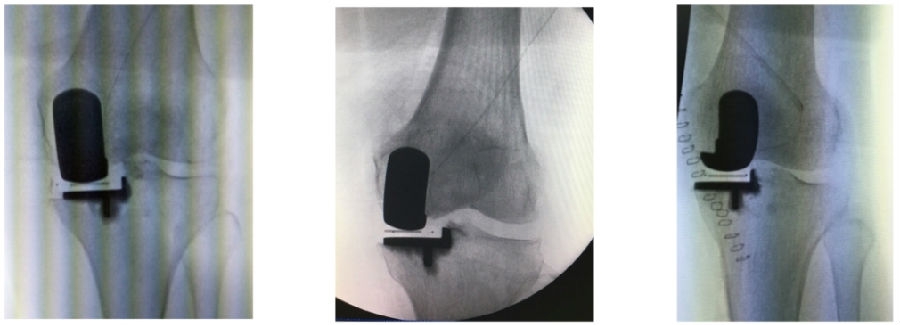

12、术后拍片

目前,笔者团队已经做了70多例,在早期探索过程中可能会出现一些问题,但是之后基本上都是比较好的,术后片子比较赏心悦目。

典型病例

13、符合度验证

同时,笔者团队也在和导板公司进行合作,把用术后CT和术前CT进行匹配,来验证术前规划的偏离度有多少,包括胫骨后倾、冠状面内倾、轴面胫骨假体旋转、股骨在冠状面的角度、股骨在轴面上的旋转角度以及在矢状面上屈伸角度。

简单总结一下近期的数据,共20例患者的20例膝关节,男5人(25%),女15人(75%),左膝11例(55%),右膝9例(45%)。平均年龄69.8+5.6岁。以±3°作为整个导板设计规划与实际实施的幅度标准。术前规划与术后实际型号没有任何区别,是100%的符合度。

胫骨后倾角有95%的符合度,胫骨内翻角是100%的符合度;胫骨旋转仍然存在一个相对大的差距,但是比传统工具要更好,有70%的病人胫骨内旋角是在范围之内。

股骨在冠状面的角度上也是比较好的表现,股骨内翻角存在95%的符合度,股骨内外旋转角稍差一点,但也达到70%。目前唯一还存在不太满意的地方就是矢状面上股骨假体低头,这个角度偏差度和术前规划差距较大,有50%的准确。

上文回顾之前的一篇文献提到,实际上传统工具和机器人如果按照±2°的话,它只有最高41%的准确度,所以导板能达到目前这样的准确度已经很不错了。但是,后续还有很多需要不断改进探索的地方。